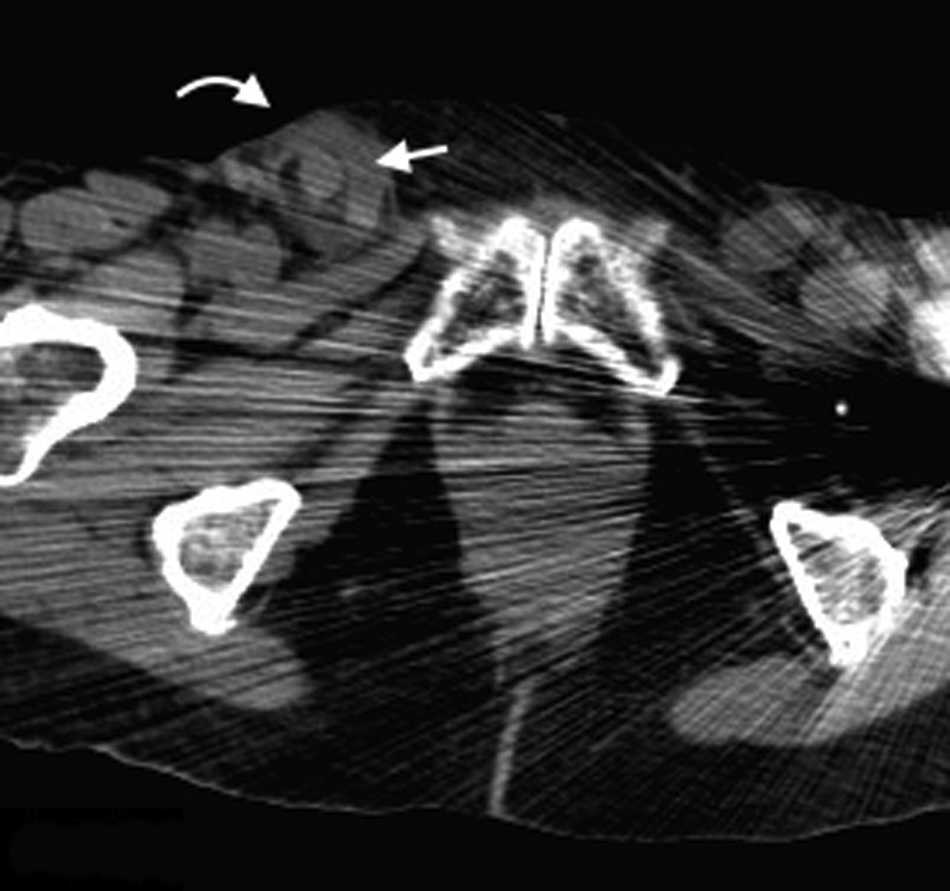

Hernia intercostal

Denominada como hernia intercostal abdominal por algunos autores, constituye una entidad rara de la que se sabe muy poco15. Produce una protrusi??n de grasa o v??sceras abdominales a trav??s de un espacio intercostal bajo, manteniendo el diafragma intacto. Se cree que sus etiolog??as m??s frecuentes son los traumatismos o las cirug??as.

Con mayor frecuencia aparece debajo del noveno arco costal y los s??ntomas por los que consultan los pacientes son hinchaz??n del t??rax inferior y dolor. Sus complicaciones son similares a las de las dem??s hernias: esto es, encarcelaci??n y estrangulaci??n (fig. 8).

El diagn??stico se hace mediante TCMD. Esta detecta el saco herniario protruyendo entre los arcos costales16.